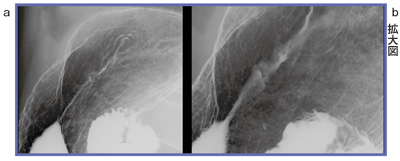

そこで,登場するのがFPD搭載デジタルX線テレビ装置である。図3,4は同一受診者の比較画像であるが,I.I.(a)に比べ,FPDの画像(b)の解像度が向上していることがわかる。また図5aは,一見すると,陥凹境界が明瞭であり,それに随伴する帯状隆起ということでは,未分化型癌のように見えるが,拡大してみると(図5b)正常粘膜よりも粒の小さな顆粒状陰影が観察され,辺縁に薄く染み出し所見が認められることから,分化型癌であることがわかる。100万画素I.I.では,このような細部の描出は難しい。